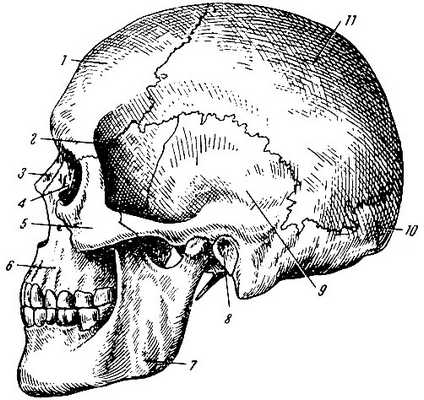

Череп (вид сбоку). 1 - лобная кость; 2 - клиновидная кость (большое крыло); 3 - носовая кость; 4 - слёзная кость; 5 - скуловая кость; 6 -

верхняя челюсть; 7 - нижняя челюсть; 8 - наружное слуховое отверстие;

9 - височная кость; 10 - затылочная кость; 11 - теменная кость